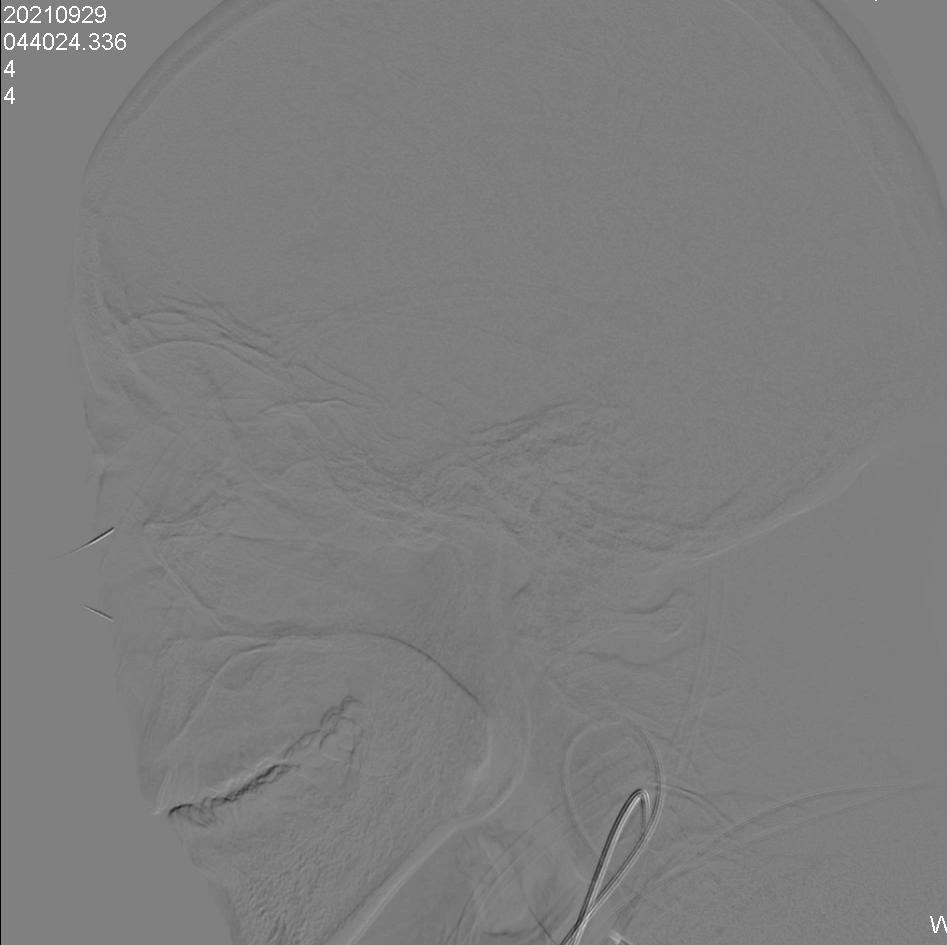

右侧颈内动脉及右侧椎动脉同时造影。

在路图指引下,沿5F中间导管送入微导丝+Echelon-10微导管至右侧椎动脉V4段,多次尝试后微导丝成功通过基底动脉闭塞段,将微导丝头端置于右侧大脑后动脉P2段。

撤除微导管,送入加奇SacSpeed®球囊1.75×12mm,由基底动脉闭塞段远端至近端依次扩张,复查造影发现基底动脉复通。

SacSpeed®球囊扩张后造影。